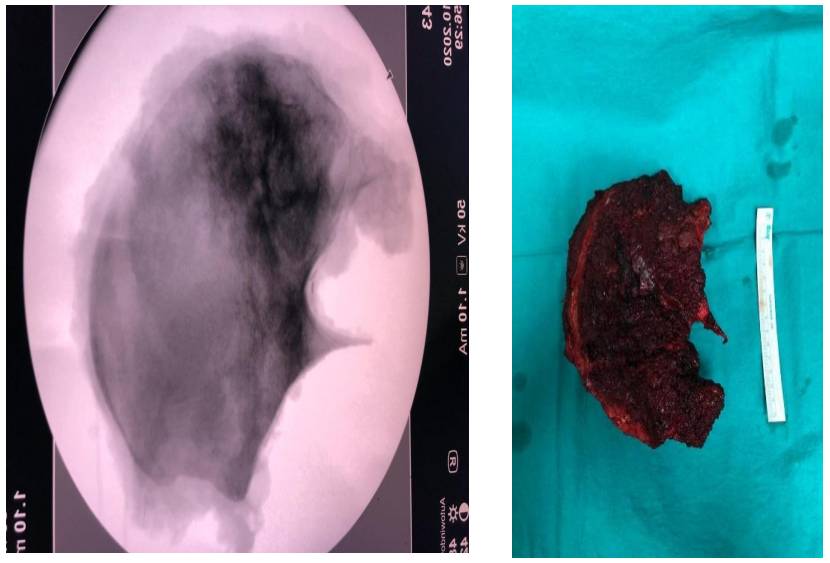

Ameliyat Esnası: Çıkarılan tümörün klinik ve skopi görüntüsü